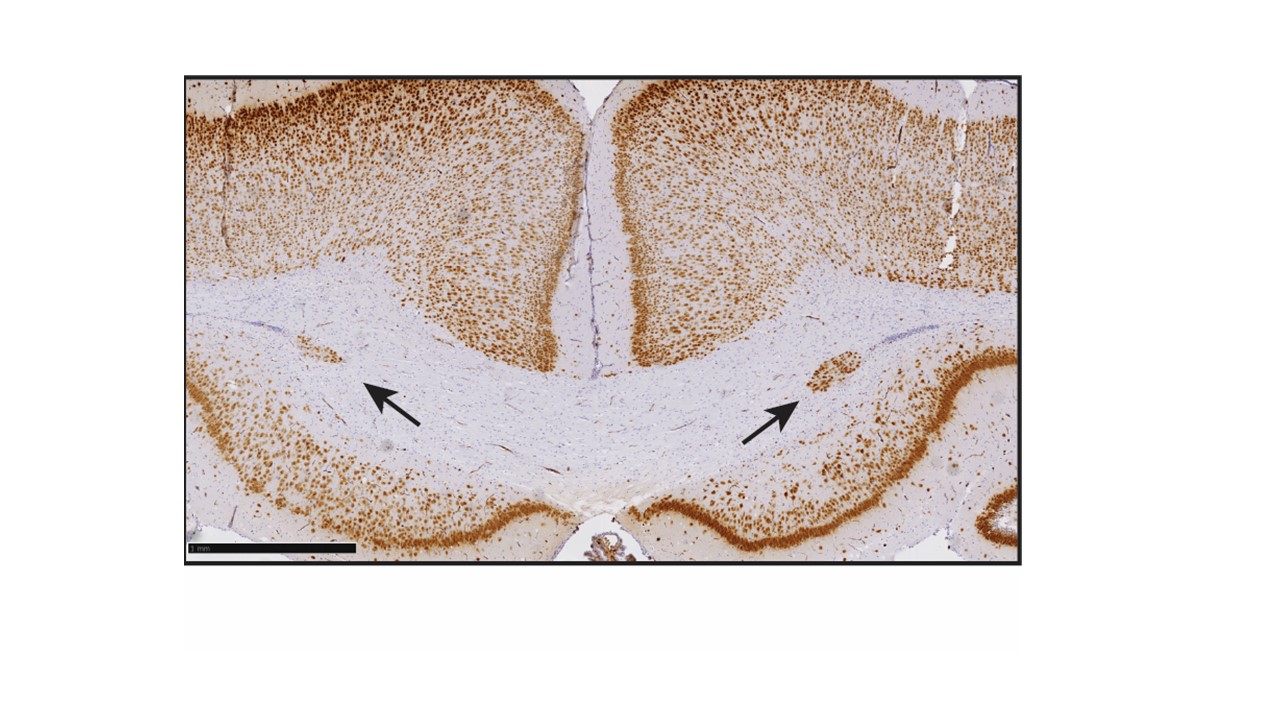

Heterotopia -misplaced cells in the corpus callosum of rat

ATHENA’s in vivo work showed that disruption of thyroid hormone homeostasis causes structural and functional brain effects mediated by TH deficiency. TH disruption altered cortical development, hippocampal gene expression, and neuronal differentiation, confirming that developmental TH deficiency drives neurodevelopmental adversity.